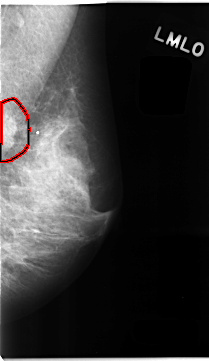

C_0107_1.LEFT_MLO

FILE: C_0107_1.LEFT_MLO.OVERLAY

TOTAL_ABNORMALITIES 1

ABNORMALITY 1

LESION_TYPE MASS SHAPE IRREGULAR MARGINS ILL_DEFINED

ASSESSMENT 5

SUBTLETY 5

PATHOLOGY MALIGNANT

TOTAL_OUTLINES 1

BOUNDARY